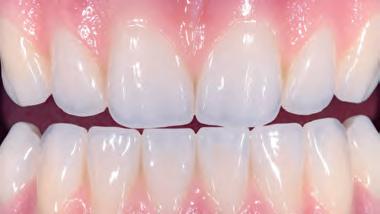

Prettau 3 Dispersive zirconia

Prettau Dispersive zirconia materials are, according to their manufacturer Zirkonzahn, characterised by a smooth, natural colour gradient built into the manufacturing process, offering a triple gradient of natural colour, translucency and flexural strength. The company says this is thanks to a special technique that does not blend colours into layers but disperses them evenly and that, with the Gradual-Triplex-Technology, a triple gradient has been developed for the new Prettau 3 Dispersive zirconia. Zirkonzahn also says that in addition to the colouring smooth gradient, translucency and flexural strength levels also change. Whereas the incisally increasing translucency results in a highly translucent incisal edge, the cervically increasing flexural strength results in an extremely high flexural strength at the tooth neck, according to the company. Accordingly, Prettau 3 Dispersive can be used for all kinds of zirconia restorations, although it is particularly suitable for monolithic rehabilitations. For a final prosthesis with a colour matching with the patient’s natural tooth shade, Zirkonzahn says their new shade guides can be used. Composed of monolithic zirconia sample teeth, they exist for all Prettau Dispersive zirconia materials and are available in the shape of a premolar as well as lower and upper incisor (also with minimal cutback for a totally customised shade guide). If the final restoration is milled out of a Prettau Dispersive zirconia blank identical to the one of the shade guide used, the company says the colour of the zirconia restoration corresponds 1:1 with the natural tooth shade of the patient.

Monolithic maxillary restoration made with Prettau 3 Dispersive zirconia (13-23).